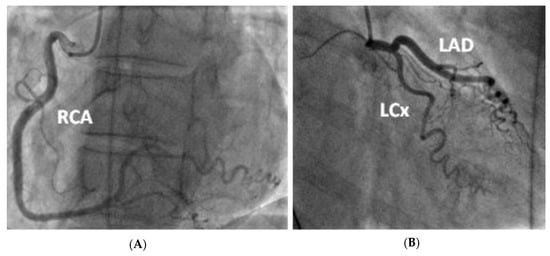

Figure 2.

(A) Posterior-anterior erect X-ray taken on initial admission in November 2019. Normal cardiothoracic ratio, normal heart size and lungs are clear with no focal abnormality. (B) PA erect X-ray taken on second admission in January 2020. No new features compared to previous X-ray.